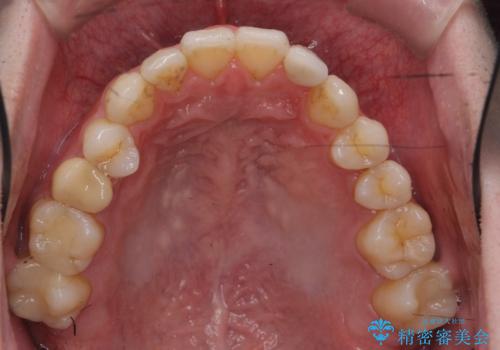

前歯の矮小歯 奥歯の反対咬合 をインビザラインで

- 上下の前歯が気になり来院。

左上2が矮小歯で小さく、また、左の奥歯が反対咬合になっていました。

左上2番はセラミッククラウンで反対側と同じ大きさにしました。

今回は下の前歯を1本抜くことで、下の奥歯をしっかり内側に傾けて治療を行いました。